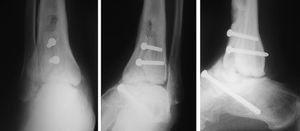

En las fracturas del cuerpo del astrágalo (7 casos) se realizó reducción abierta mediante un abordaje medial con osteotomía del maléolo tibial para visualizar todos los planos de la fractura y fijación interna (RAFI) con tornillos o agujas de Kirschner, o ambos. En 2 casos se realizó un abordaje bilateral debido a la complejidad de la fractura (fig. 6).

Fig. 6. --Fractura abierta de cuello de astrágalo (tipo III de Hawkins) y tratamiento realizado. Radiografías a los 16 meses.

Fig. 6. --Open fracture of the astragalus neck (Hawkins type III) and treatment carried out. Radiographies at 16 months.